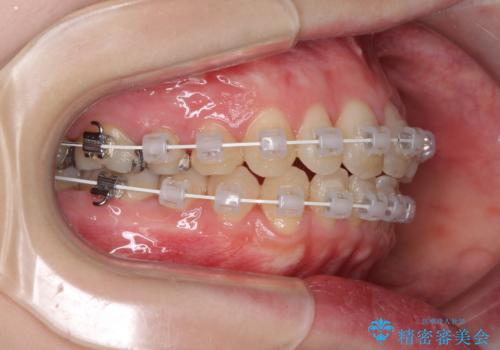

- 矯正装置

- 審美装置

治療途中で出産されたこともあり、当初予定よりも終了までに期間がかかってしまいました。

舌を前方に突出する癖があったため、上下前歯がなかなか接触しなかったことも治療期間が伸びた要因です。